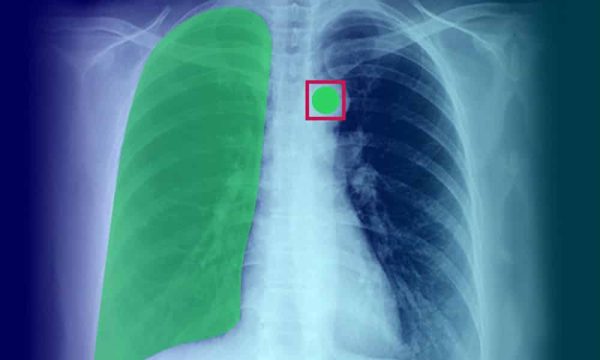

Мы занимаемся разработкой систем анализа медицинских изображений уже несколько лет, и за это время мы накопили ценный опыт. Мы разрабатываем алгоритмы для выявления различных заболеваний на рентгеновских снимках, томограммах и ультразвуковых сканах. Мы тесно сотрудничаем с врачами, чтобы понять их потребности и разработать решения, которые действительно помогают им в работе.

Один из наших проектов – это система автоматического выявления пневмонии на рентгеновских снимках. Мы разработали алгоритм, который может с высокой точностью определять наличие признаков пневмонии, что позволяет врачам быстрее и точнее ставить диагноз. Эта система уже используется в нескольких больницах и помогает спасать жизни.